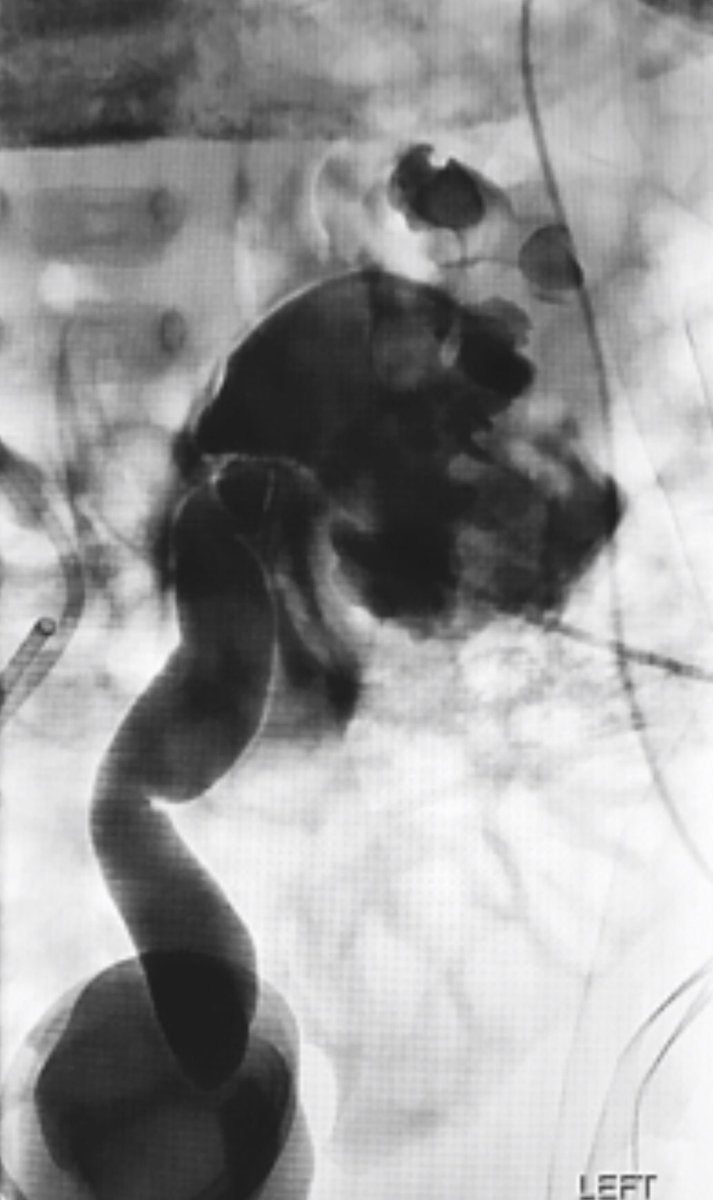

Paediatric nephrostomy

-Congenital obstruction – PUJ, VUJ

xDistorted anatomy – calyx puncture vs pelvic puncture

xRupture

– very dilated PCS,

- guidewire exchange,

- infection

xNon dilated PCS: challenging to get in